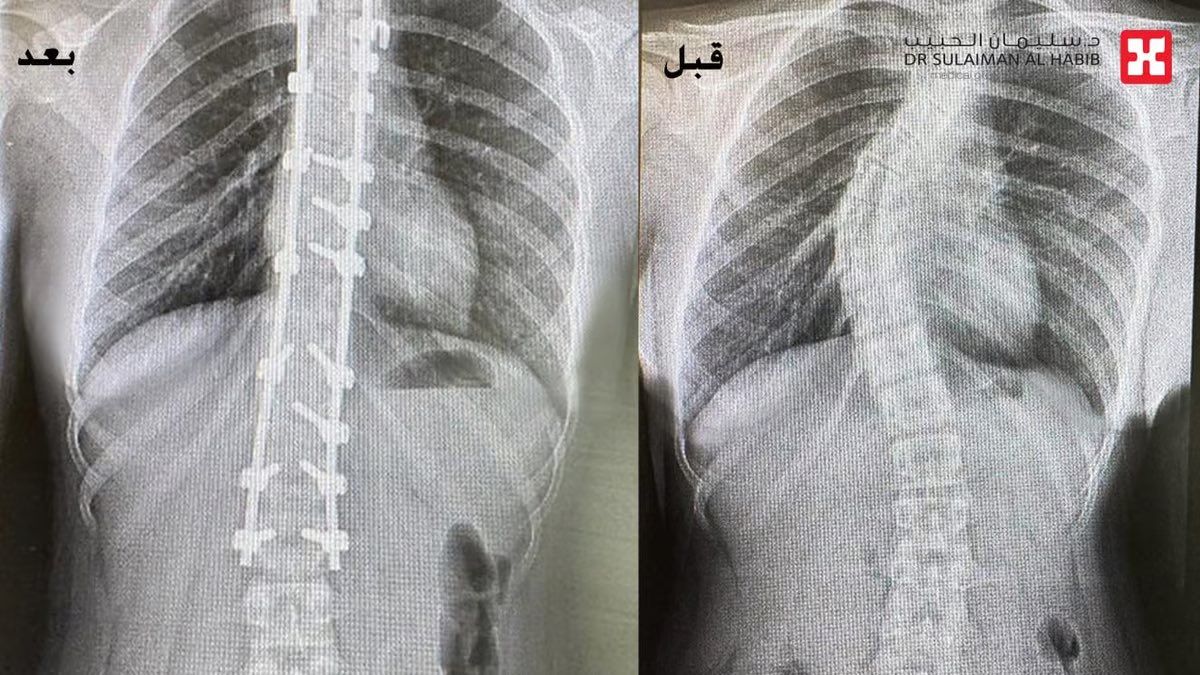

أنهى مستشفى الدكتور سليمان الحبيب بالعليا، معاناة فتاة تبلغ من العمر 12 عاماً، كانت تعاني من تشوه في العمود الفقري “جنف” ناتج عن تقوس شديد بالمنطقة الصدرية ، وقد تسبب لها هذا الأمر في مشكلة نفسية خاصة مع ارتفاع الكتف الأيمن عن الأيسر أثناء المشي، وكذلك اعاقتها عن أداء دراستها وممارسة أنشطتها اليومية الإعتيادية، بالإضافة إلى وجود مشاكل في النوم نتيجة شدة الإنحراف وزاويته. ذكر ذلك الدكتور واصف السباعي استشاري جراحة العظام والعمود الفقري الحاصل على الزمالة البريطانية رئيس الفريق المعالج.

والذي أضاف بأنه فور وصول الفتاة لمركز طب وجراحة المخ والأعصاب والعمود الفقري بالعليا، تم السماع لشكواها وإخضاعها للفحص السريري، والذي أبان أنها تعاني من آلام حادة ومتزايدة منذ 3 سنوات، حيث تم إجراء أشعة الرنين المغناطيسي (M.R.I) على كامل منطقة الظهر، بالإضافة إلى التحاليل المخبرية، وقد أكدت النتائج وجود اعوجاج شديد بالمنطقة الصدرية يبلغ زاويته (62) درجة في جهة اليمين بالعمود الفقري مع تحدب وتشوه بالقفص الصدري، وهو الأمر الذي سبب عدم استواء الكتفين الأيمن أثناء المشي.

وأفاد الدكتور السباعي أن الفريق الطبي المعالج قام بإجراء دراسة وافية للتاريخ المرضي ونتائج الفحوصات، وانتهى إلى ضرورة التدخل الجراحي العاجل لايقاف الانحراف المتزايد للعمود الفقري وتقويمه والحد من الأعراض والمضاعفات المتفاقمة. موضحاً أن الجراحة استغرقت 5 ساعات متواصلة تحت التخدير العام، وتم فيها استخدام تقنيات متطورة للمساعدة في تقويم الفقرات وتعديلها بالإضافة إلى جهاز المراقبة العصبية ، وقد تمكن الفريق الطبي من تقويم العمود الفقري بنسبة 96%، علاوة على تثبيت ودمج الفقرات بشكل ممتاز. ولله الحمد تكللت جهود الفريق الطبي بالنجاح دون أية مضاعفات، إذ استطاعت الفتاة الوقوف بعد 24 ساعة فقط من العملية بمساعدة العلاج الطبيعي، وعادت لمنزلها بعد أن تلقت رعاية طبية فائقة على مدار 5 أيام، وبدأت تمارس حياتها بصورة طبيعية .